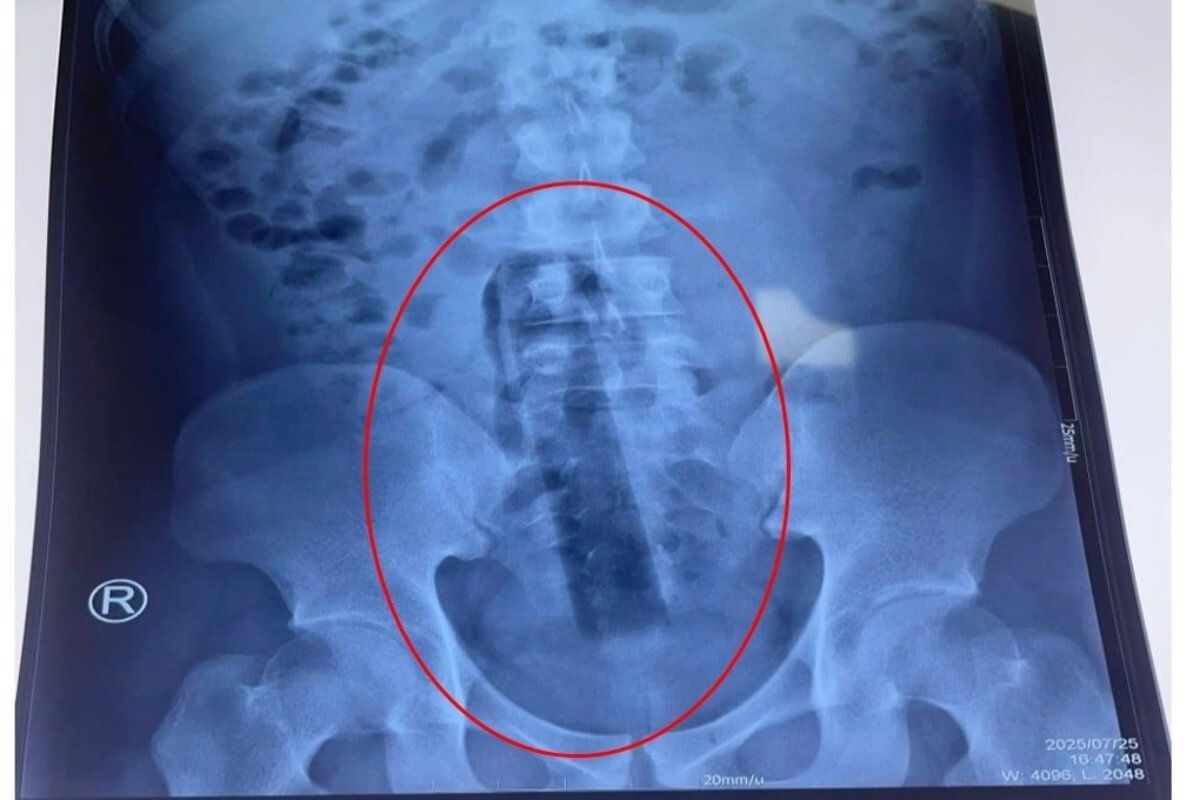

https://poste-vn.com/news/2025-08-06-20466ホーチミン市の115人民病院は4日、23歳の男性患者がモップの柄(約15cm)を直腸内に挿入し、自力で取り出せず緊急搬送されたと発表した。

患者は激しい肛門痛と腹部膨満を訴え、X線検査により異物が直腸深部に達していることが判明したため、全身麻酔下で外科手術が実施され、異物が摘出された。